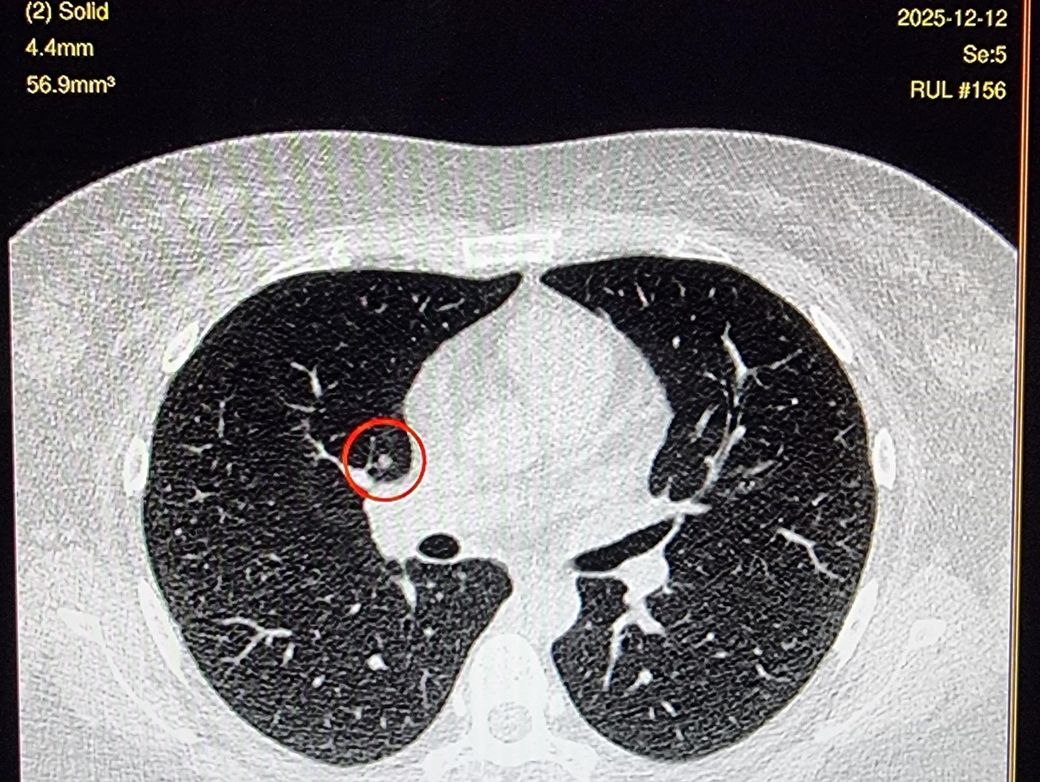

25년 결절 판독 Little change of a tiny solid perifissural nodule in RUL (2-52).

: probably, benign.

24년 결절 판독 오른쪽 indeterminate

고형이애요 간유리에요 반고형간유리 같나요